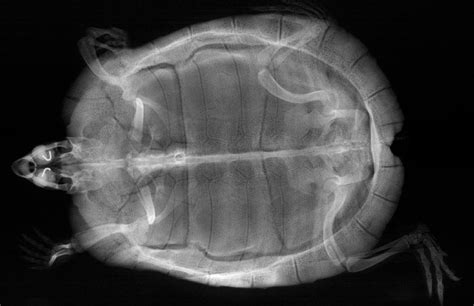

So, how exactly do we get to see those amazing inside views of our turtle pals? It’s all thanks to the incredible technology of turtle x-rays . Basically, x-rays use a special kind of radiation that can pass through soft tissues like skin and organs but gets absorbed more by denser materials like bone. When a turtle is placed in front of an x-ray machine, the radiation beams pass through its body. Different parts of the body absorb this radiation to varying degrees. The parts that absorb more radiation (like bones and dense foreign objects) block the x-rays, while softer tissues let more pass through. These differences in absorption are then captured on a special detector, creating a black-and-white image that shows us the internal structures. Think of it like a shadow puppet show, but for the inside of a turtle! It’s a pretty standard procedure in veterinary medicine for reptiles, and it’s crucial for diagnosing a range of issues, from internal injuries and infections to problems with their digestive system or reproductive organs. The quality of the image depends on several factors, including the turtle’s size, the x-ray machine’s power, and the positioning of the turtle. Vets often take multiple views, usually a lateral (side) view and a ventrodorsal (from top to bottom) view, to get a comprehensive understanding of the turtle’s anatomy and any abnormalities. It’s a bit like looking at a 3D object from different angles to really get a feel for its shape and structure. We often need to sedate or anesthetize the turtle to ensure it stays perfectly still during the scan, which is vital for obtaining clear, diagnostic-quality images. Any movement can blur the image, making it difficult to interpret. So, while it might seem simple, there’s a whole lot of science and care that goes into capturing those revealing turtle x-rays .

Now, for the real nitty-gritty: what are vets actually looking for when they examine turtle x-rays ? It’s not just about spotting a weird shape; it’s a careful, detailed analysis. First off, they’re scrutinizing the skeletal structure . This includes the bones of the limbs, the spine, and critically, the carapace (top shell) and plastron (bottom shell). They’re checking for proper mineralization – are the bones dense and white, or are they looking a bit gray and translucent? This is a key indicator of metabolic bone disease. They’ll also look for any fractures or dislocations , whether from trauma or underlying weakness. The alignment of the bones is also super important; any unnatural angles or breaks in the continuity of the bone are red flags. Next up is the coelomic cavity . This is where the magic happens – vets can see the outlines of internal organs like the liver, kidneys, and heart, although their details aren’t always super clear on a standard x-ray. What they can often see are abnormalities. This includes foreign bodies – those pesky swallowed objects we talked about. They’ll appear as distinct, often dense shapes in the digestive tract. They also look for signs of organ enlargement or unusual masses , which could indicate tumors or other growths. In females, the presence and position of eggs are a major focus. They’ll count them, assess their size, and check if they are properly formed or if there are signs of resorption (where the body reabsorbs egg material, a serious complication). For respiratory issues , vets examine the lungs. While not always perfectly clear, signs like increased opacity (whiteness) in the lung fields can suggest fluid accumulation or pneumonia. Finally, they’ll assess the overall body condition . Are the bones looking healthy? Is there any evidence of organ displacement? It’s a holistic view, piecing together all the visual clues from the turtle x-rays to build a picture of the turtle’s health. It’s a bit like being a detective, using the x-ray image as the crime scene to uncover what’s really going on inside.